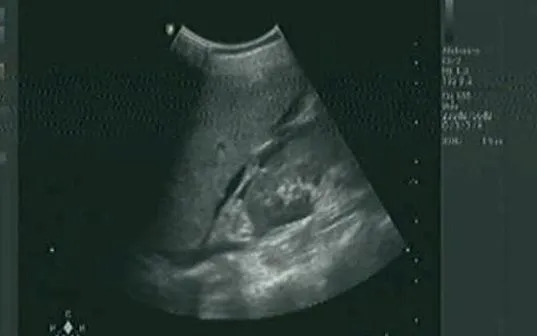

Theo các bác sĩ Trung tâm Y tế khu vực Thuận An (TP Hồ Chí Minh), siêu âm bụng là công cụ chẩn đoán hình ảnh không xâm lấn, giúp phát hiện sớm tình trạng thoát huyết tương - nguyên nhân chính dẫn đến sốc trong SXH Dengue. Những dấu hiệu cảnh báo trên siêu âm gồm:

Tràn dịch màng bụng (cổ chướng): Dịch quanh gan, túi cùng Douglas - báo hiệu thoát huyết tương rõ rệt.

Tràn dịch màng phổi: Thường xuất hiện ở đáy phổi phải, cảnh báo bệnh tiến triển nặng.

Gan to: Gan phải to >1,5 cm dưới bờ sườn, nhất là ở trẻ em.

Dày thành túi mật ≥3 mm: Dấu hiệu sớm, có độ nhạy cao trong tiên lượng sốc Dengue.

Tại Trung tâm Y tế khu vực Thuận An, chỉ trong tháng 9, Khoa Chẩn đoán hình ảnh đã ghi nhận nhiều ca SXH ngày thứ 3-7 có dấu hiệu cảnh báo trên siêu âm.

Trường hợp bệnh nhân N.T.K. (sinh năm 2003): Dày thành túi mật 7 mm, dịch ổ bụng lượng ít, tràn dịch màng phổi phải.

Bệnh nhân Đ.T.D.M. (sinh năm 2007): Dày thành túi mật 11 mm, tràn dịch màng phổi phải lượng ít - được chẩn đoán SXH Dengue nặng, đã qua sốc sau điều trị tích cực.